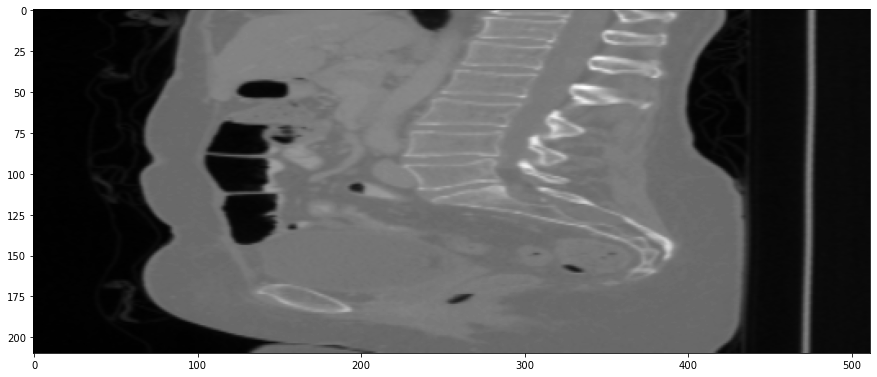

Refer to caption

(a) True Thick-slice image

(b) Simple Averaging

RMSE: 0.0357, PSNR: 34.9781

(c) Gaussian Averaging

RMSE: 0.0454, PSNR: 32.8866

(d) Direct Downsampling

RMSE: 0.0486, PSNR: 32.2861

(e) Proposed Simulation

RMSE: 0.0070, PSNR: 49.1774

Figure 4: Sagittal-plane thick-slice image quality comparison across four simulation methods.